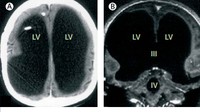

Seorang pria 44 tahun di Prancis mengalami kelainan pada otaknya yang ternyata berukuran kecil. Ia mengalami penumpukan cairan di tengkorak dan menyisakan sangat sedikit jaringan otak tipis. (Foto: The Lancet Journal)